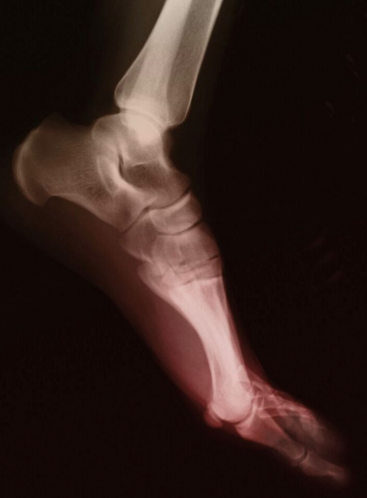

Atypical Fractures Associated With Long-Term Bisphosphonate Use

Jerome Reichmister, MD; Peter Jay, MD

Seniors are at risk of developing idiopathic osteoporosis and secondary osteoporosis subsequent to various medical conditions.